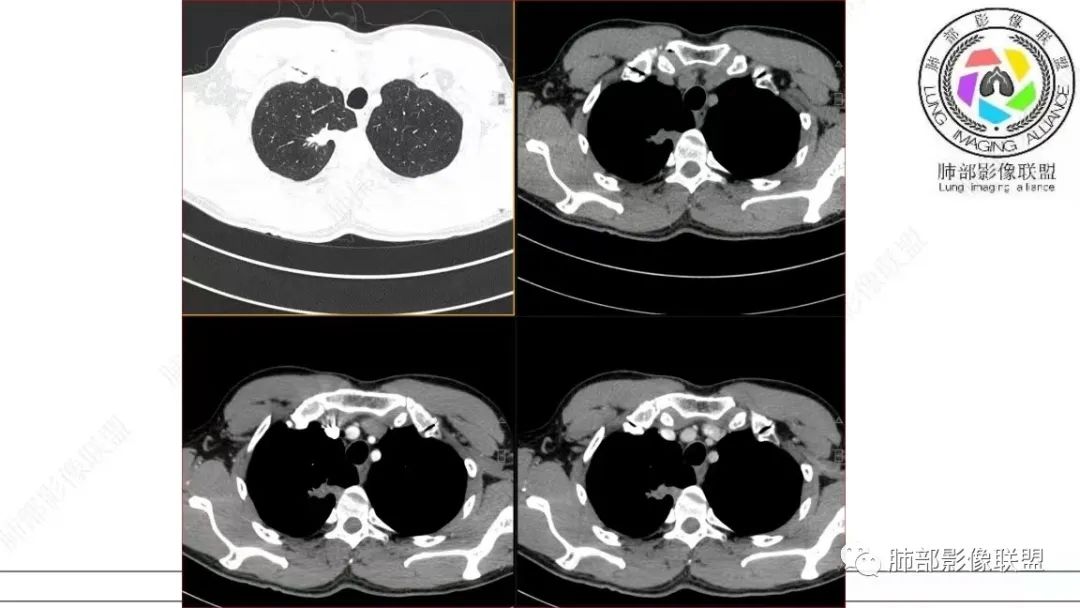

还是和病变成分有关。在肿瘤当中,或者上皮间质转换比较明显等,可以有不同的强化方式。当然也可以表现为延迟强化,可以动脉期明显强化。和肿瘤的具体类型,以及具体病变的病理成分有关。多层面观察,病变是明确有细支气管进入的,而且明确的有铸型的低密度粘液栓。

总结一下:肺内,周围型病变,含有黏液/纤维的,有收缩力的,支气管进入,有粘液栓形成的病变。常见疾病谱当然就是腺癌、特别是结节型的黏液腺癌,还有一些非特异性的慢性炎、结核等。容易形成支气管粘液栓的病变很多,慢性病变中,除了非特异性感染,一些细菌,比较常见的就是结核、曲霉。但是,支气管进入,有粘液栓形成的,周围型,肿瘤性病变,却少之又少。疾病谱中,最常见的就是气管腔内占位,以远粘液栓是继发改变。比如鳞癌、类癌。

在细支气管腺瘤的文献中,病例较少,没有看到过提到有粘液栓形成的病例描述。细支气管腺瘤的病理要点中,1,可以见到细支气管进入病灶。2.双层细胞。细支气管水平的病变,当然就可以有纤毛,有可以分泌黏液的细胞。在细支气管腺瘤中,形成的粘液,可以弥散在组织间隙,也可以聚集,形成粘液湖。更容易经过细支气管排出,形成空洞。类似于腺癌的空泡。这个病例虽然有延迟强化,收缩力比较强,也有支气管粘液栓,但是比较难解释这么低密度的,有延迟强化的,可疑粘液成分。